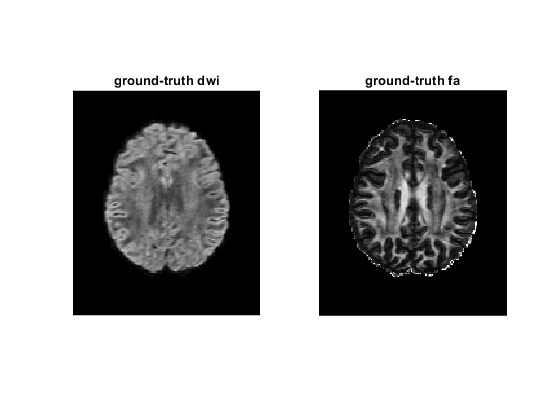

figure;

subplot(1, 2, 1)

imshow(rot90(diff_gt(:, :, 35, 2)), [0, 4000])

title('ground-truth dwi');

dtimetrics = decompose_tensor(tensor_gt, mask);

fa = dtimetrics.fa;

subplot(1, 2, 2)

imshow(rot90(fa(:, :, 35)), [0, 1])

title('ground-truth fa');